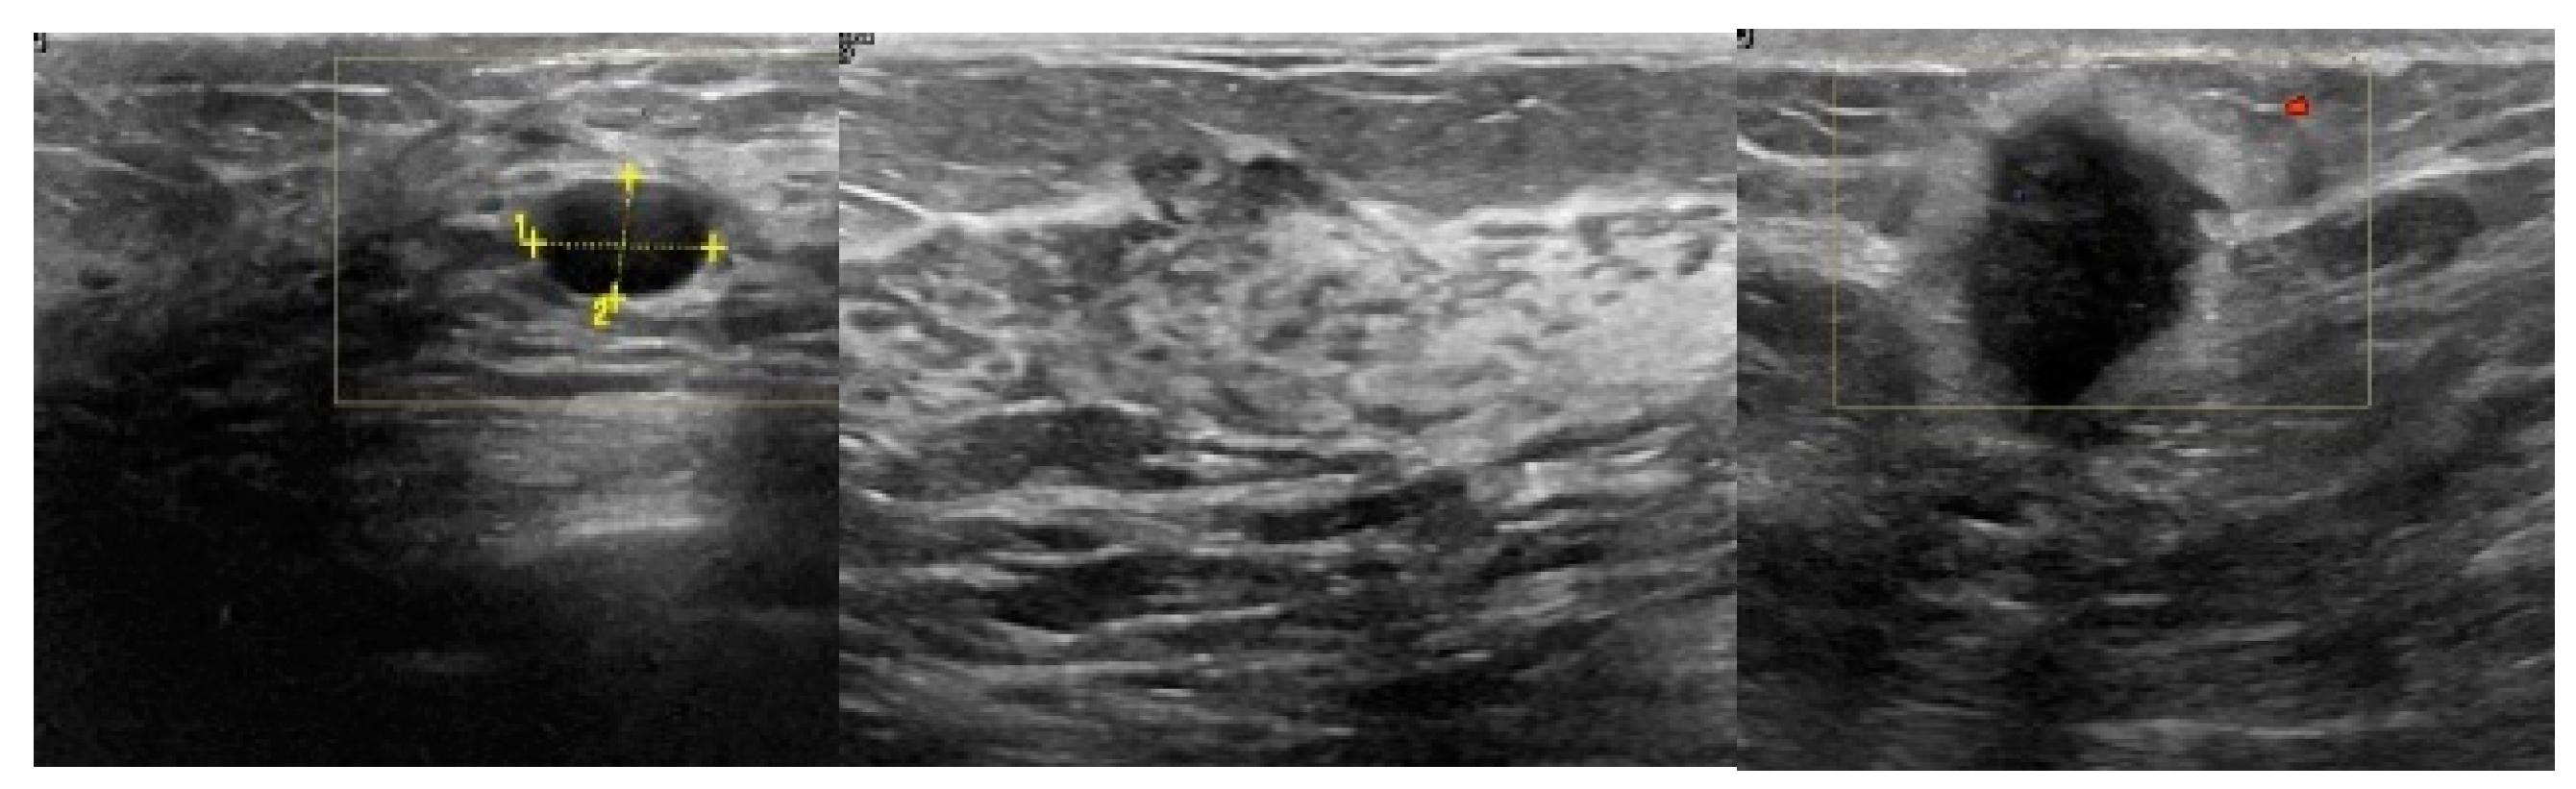

2.1. Breast Ultrasound Image Data Acquisition

3.2. Image Synthetic Augmented by WGAN